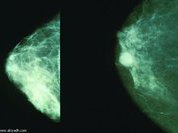

В британском, и не только, обществе уже давно идут дебаты вокруг оправданности обязательного массового скрининга женской части населения на рак молочной железы. У части специалистов вызывает сомнение как эффективность этого метода для раннего выявления заболевания, так и соблюдение баланса между приносимой им пользой и вредом для здоровья.